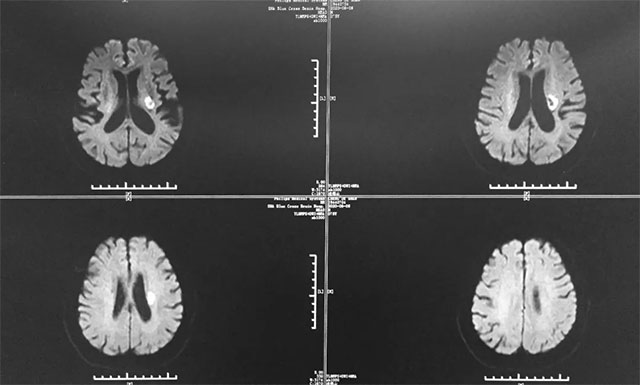

▲ 胡先生多发性脑梗,情况不容乐观

据戴秀珍主任回忆,胡先生刚入院时其脑梗还是比较严重的,患者属于多发性脑梗,并多处血管狭窄,致使其右侧肢体功能障碍。尤其是右侧上肢肢体,近端肢体肌力为2级,其远端肢体肌力却为0级,而且右上肢还伴有神经性水肿;其下肢肢体肌力为3级,不能站立和行走,并出现了言语含糊症状。